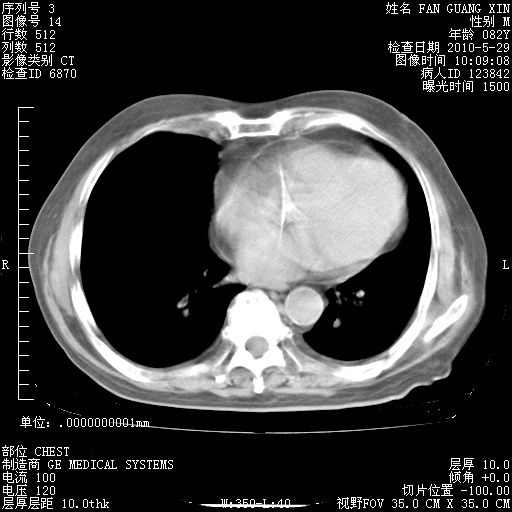

再治疗10天后的肺部CT

从白细胞总数和中性比例看好像合并感染。肺部纹理好像比上次多,支气管炎?其他感染?

阅读此次胸部CT,肺间质渗出性改变较入院时有吸收。目前从体温、白细胞、中性分叶明显增高,肯定存在细菌感染(发生医院感染哦,若无消化道及泌尿系统等感染的依据,肺部感染可能大)。若你院头孢哌酮舒巴坦钠耐药率较高,同意你的方案,若48小时体温仍高,可考虑使用碳青霉稀类抗菌药物,同时可予超声雾化、注意滴数时加大液体量。白蛋白33.30g/L较低哦,需加强营养等支持治疗。